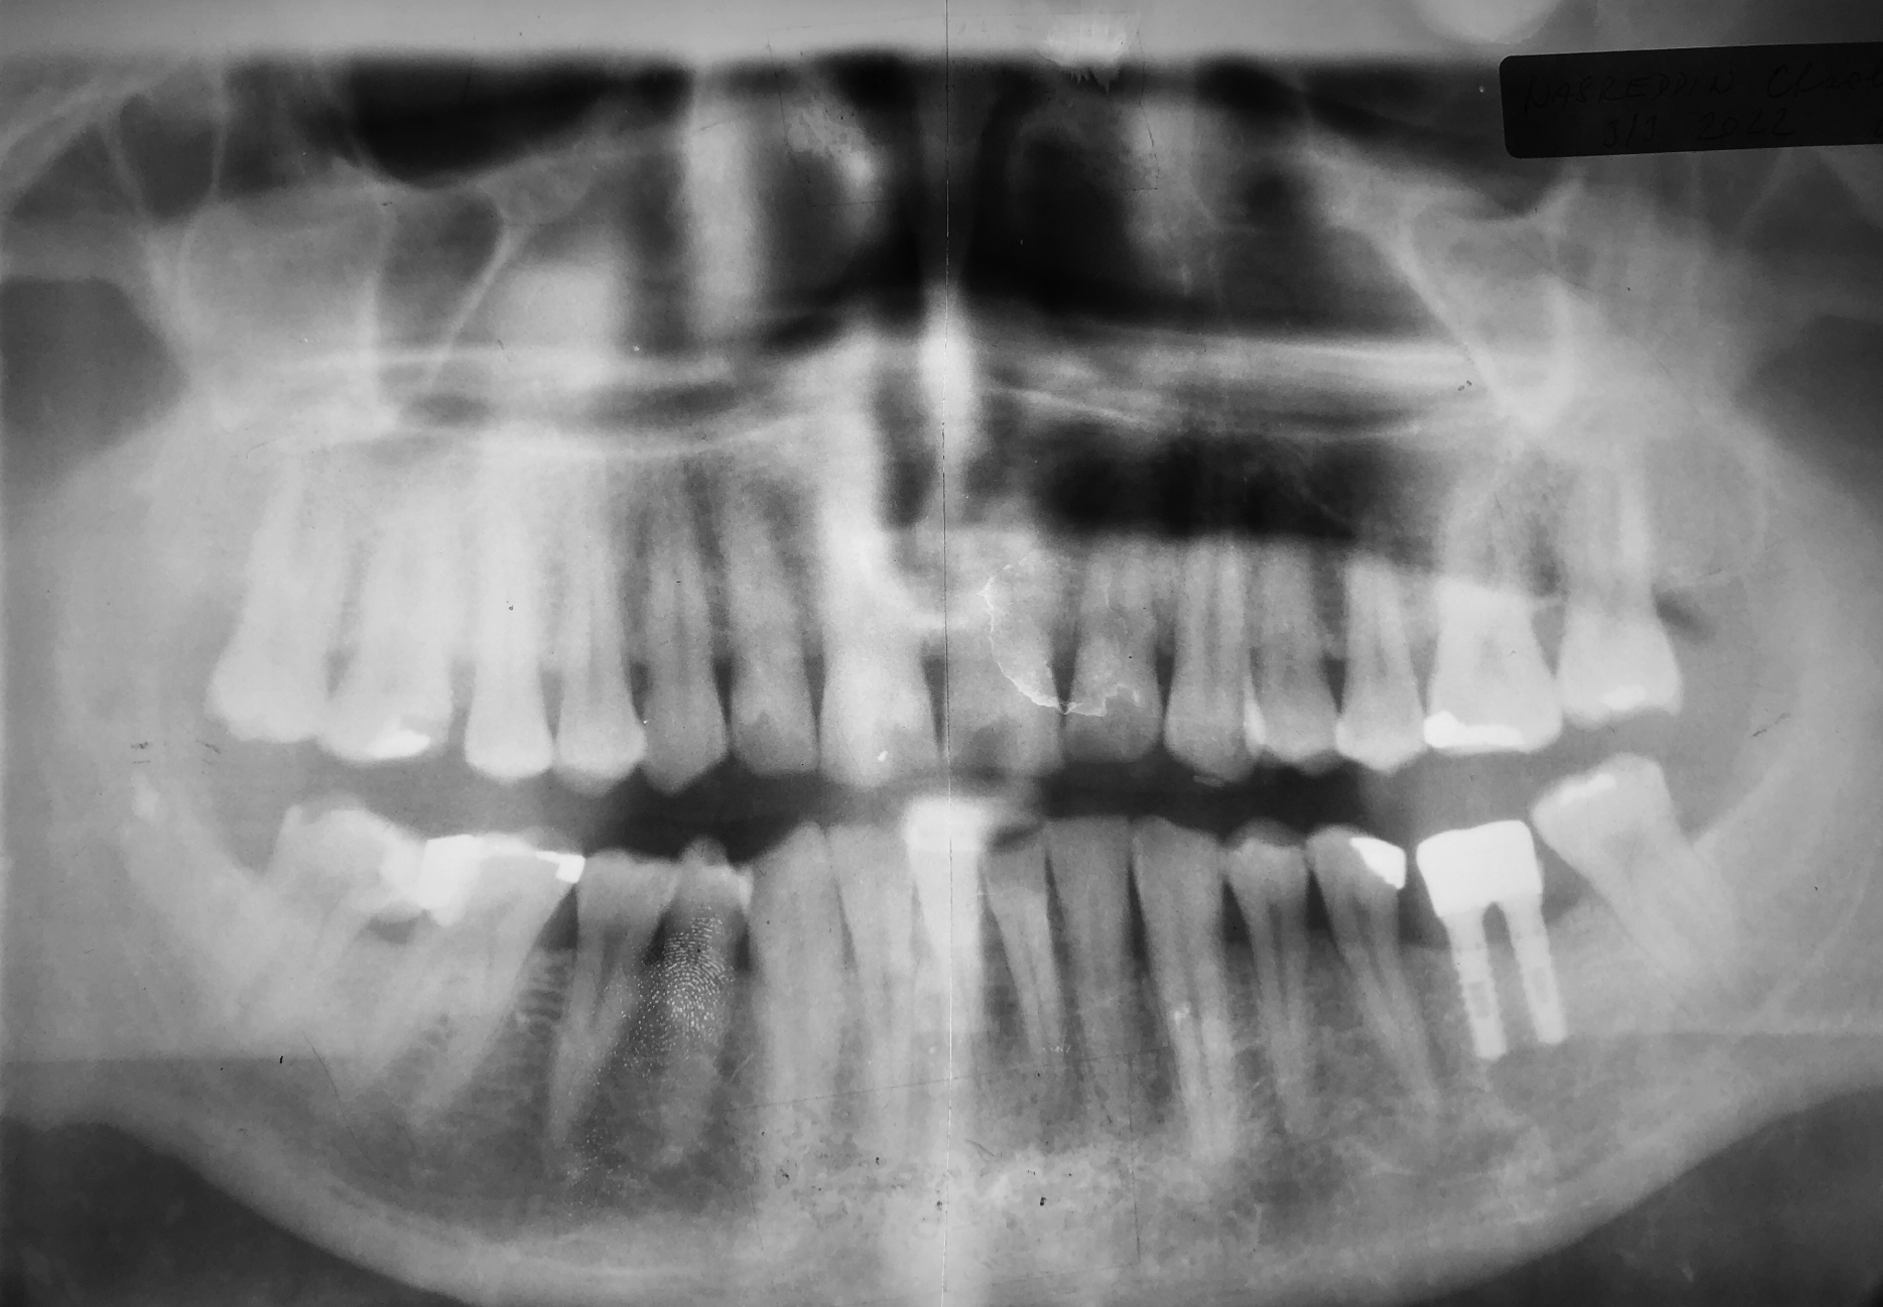

Röntgenaufnahme aus dem Recall im März 2024. Nach 21 Jahren in Funktion wurde die Versorgung neu gestaltet. Die Implantate waren stabil und das klinische Bild ohne Befund. Die Resorption aufgrund der Kontrollaufnahme war 0 mm.